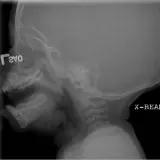

PACS์—์„œ ๊ธฐ๋Œ€ํ•  ์ˆ˜ ์žˆ๋Š” ๋ชจ๋“  ๋„๊ตฌ๋ฅผ ๊ฐ–์ถ˜ ์™„์ „ํ•œ ์ธํ„ฐ๋ž™ํ‹ฐ๋ธŒ ์ฆ๋ก€ — ์Šคํฌ๋กค, ์œˆ๋„์šฐ ์กฐ์ ˆ, ํ™•๋Œ€/์ถ•์†Œ, ํŒจ๋‹, ๊ณ„์ธก, ROI, ์ „์ฒด ํ™”๋ฉด ๋ชจ๋“œ๊นŒ์ง€ ์ง€์›ํ•ฉ๋‹ˆ๋‹ค.

์‹ค์ œ PACS ์›Œํฌ์Šคํ…Œ์ด์…˜์ฒ˜๋Ÿผ ์Šคํฌ๋กค, ํŒจ๋‹, ์œˆ๋„์šฐ ์กฐ์ ˆ, ํ™•๋Œ€/์ถ•์†Œ๊ฐ€ ๊ฐ€๋Šฅํ•ฉ๋‹ˆ๋‹ค